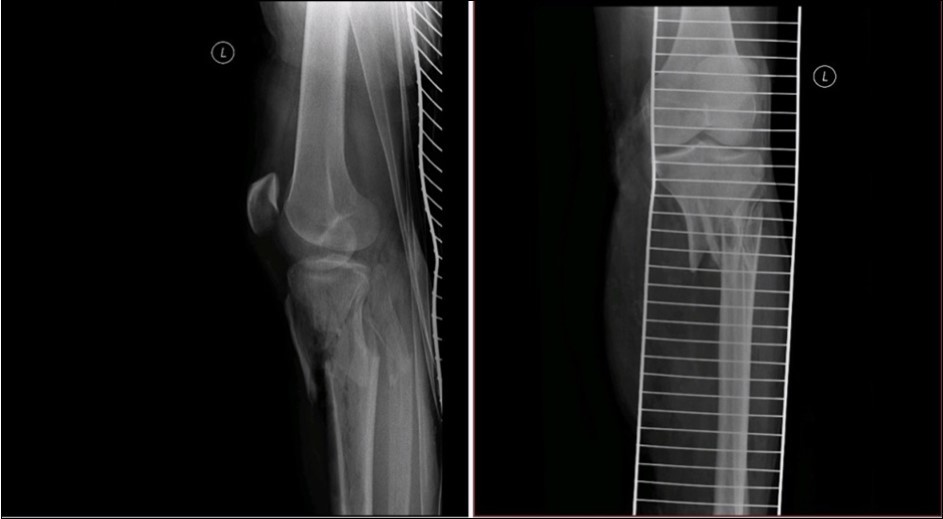

Figure 33. X-ray documentation of the whole treatment of tibia fracture. External fixation was used throughout the treatment until bone was healed. From 9.October 2015 to 2.February 2017